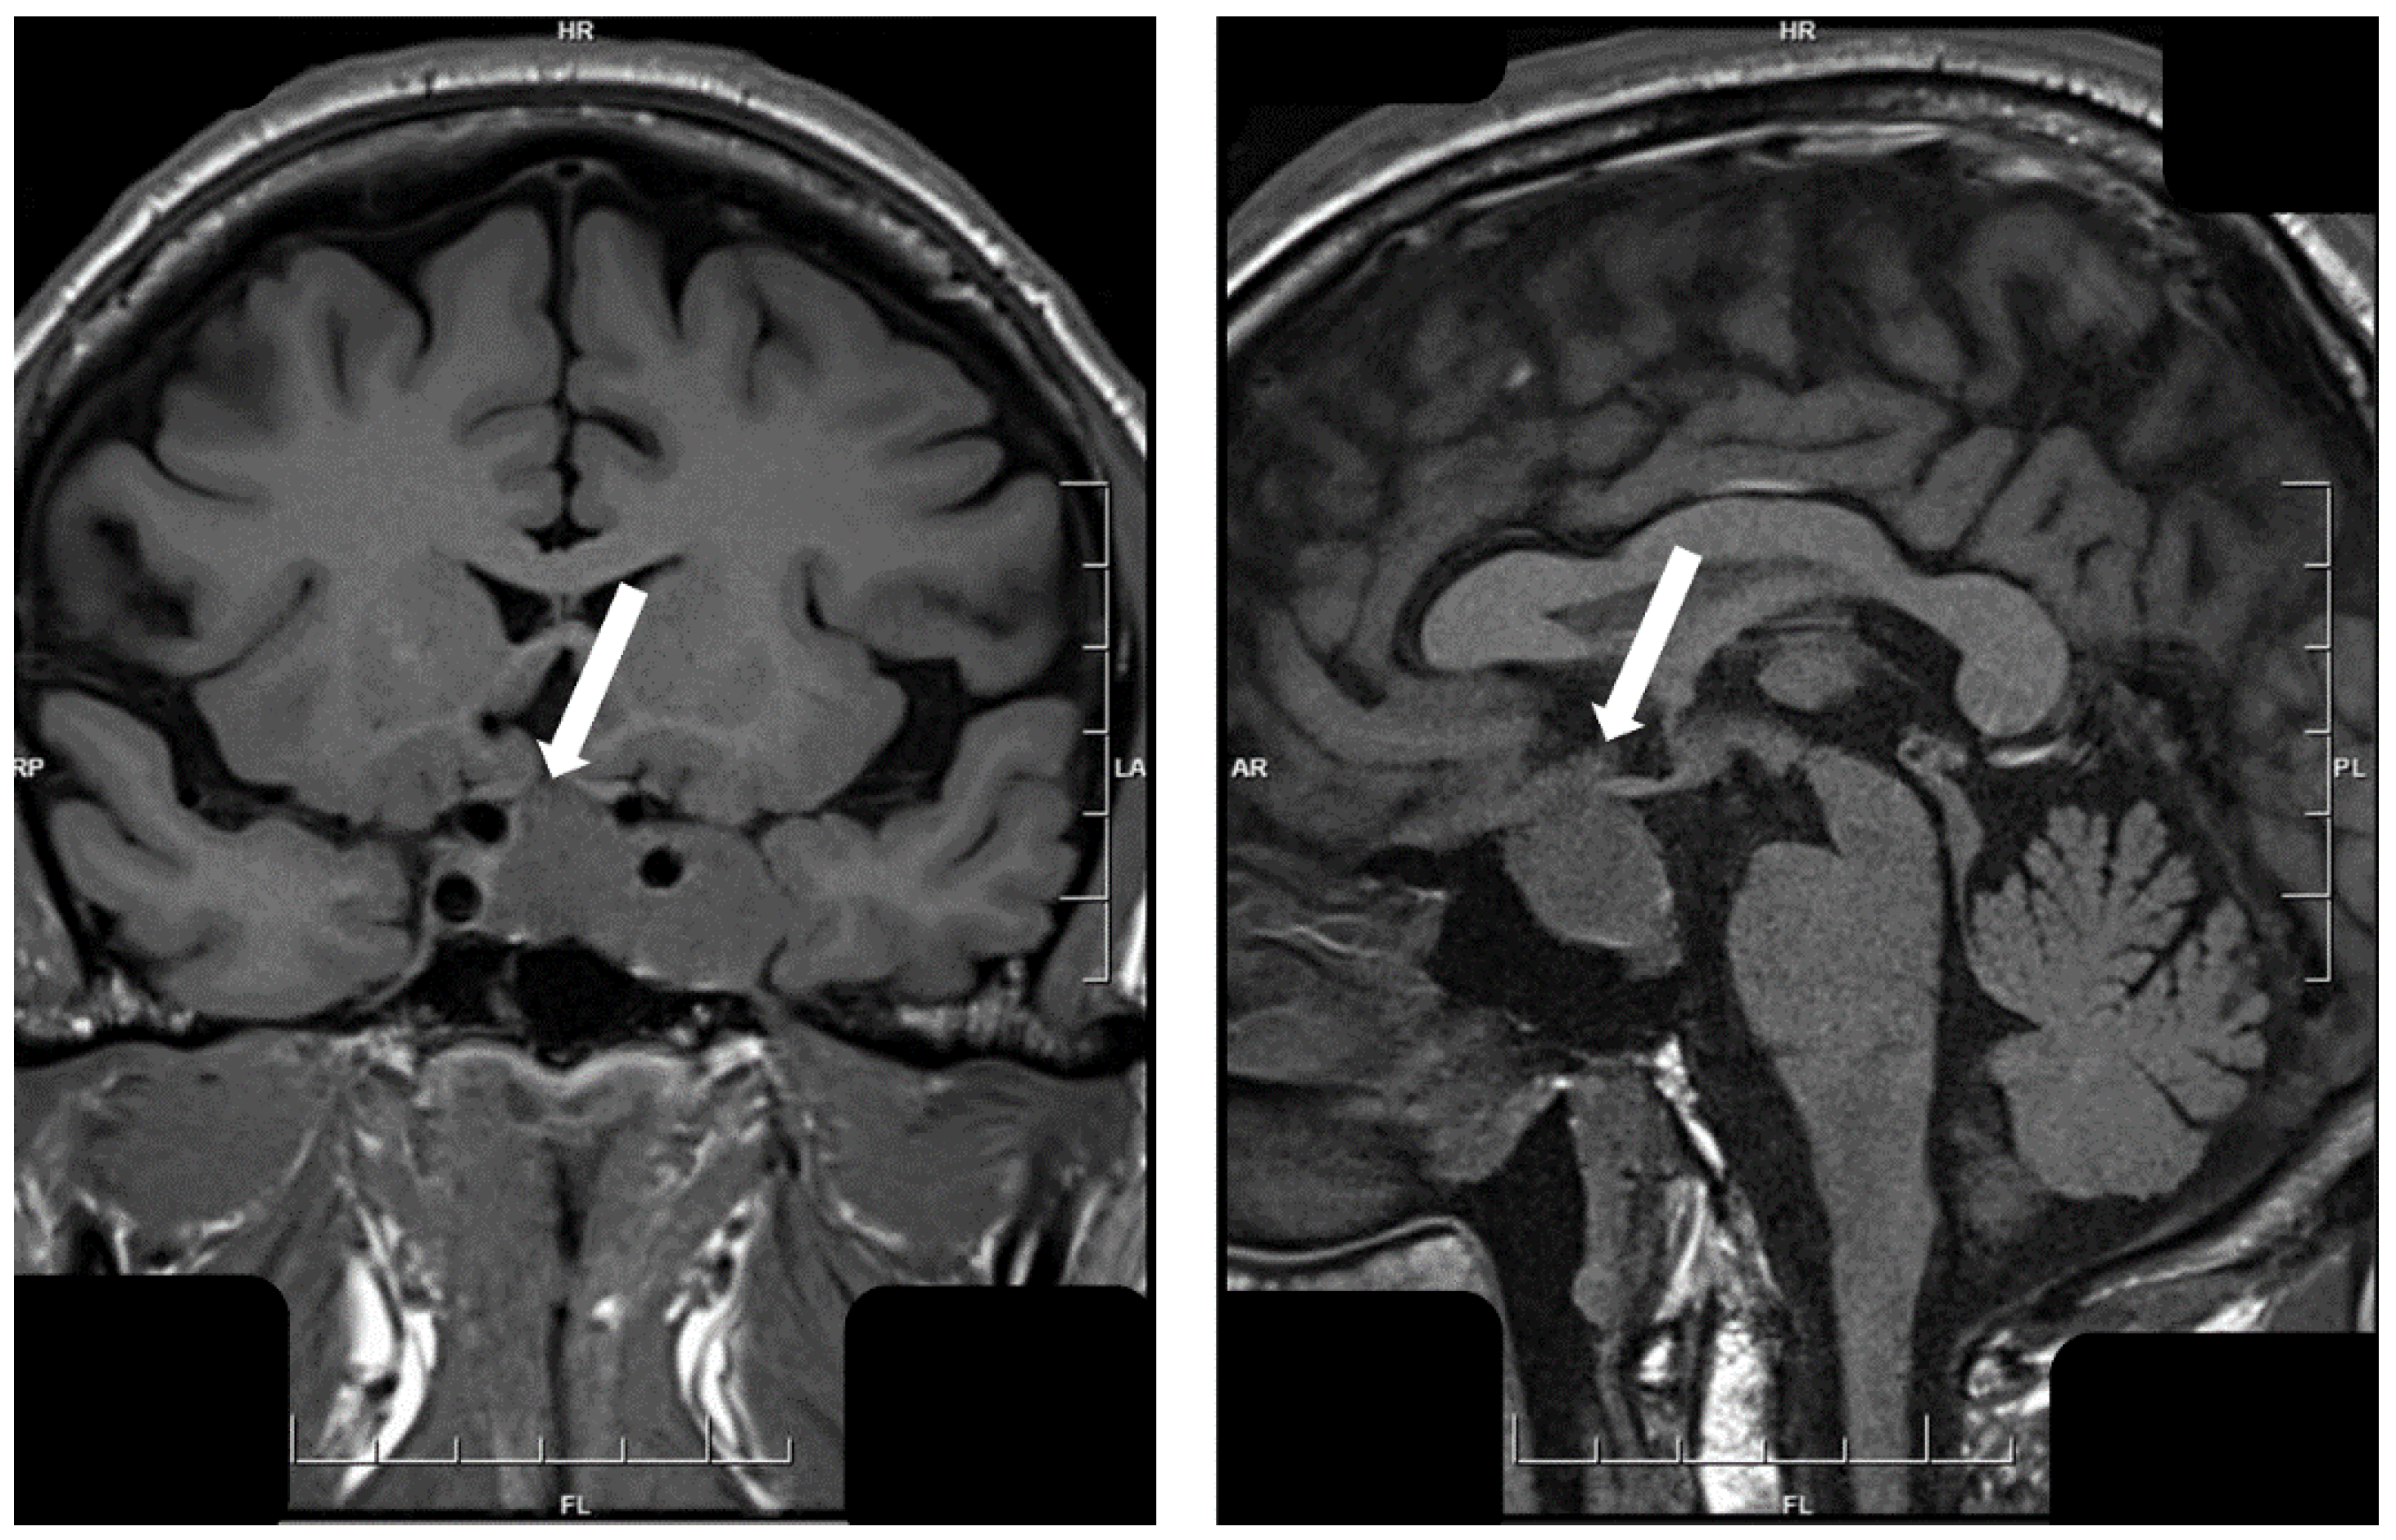

- Asa, S.L.; Kucharczyk, W.; Ezzat, S. Pituitary acromegaly: Not one disease. Endocr. Relat. Cancer 2017, 24, C1–C4. [Google Scholar] [CrossRef] [PubMed]

- Heck, A.; Ringstad, G.; Fougner, S.L.; Casar-Borota, O.; Nome, T.; Ramm-Pettersen, J.; Bollerslev, J. Intensity of pituitary adenoma on T2-weighted magnetic resonance imaging predicts the response to octreotide treatment in newly diagnosed acromegaly. Clin. Endocrinol. (Oxf.) 2012, 77, 72–78. [Google Scholar] [CrossRef]

- Hagiwara, A.; Inoue, Y.; Wakasa, K.; Haba, T.; Tashiro, T.; Miyamoto, T. Comparison of growth hormone-producing and non-growth hormone-producing pituitary adenomas: Imaging characteristics and pathologic correlation. Radiology 2003, 228, 533–538. [Google Scholar] [CrossRef] [PubMed]

- Potorac, I.; Petrossians, P.; Daly, A.F.; Alexopoulou, O.; Borot, S.; Sahnoun-Fathallah, M.; Castinetti, F.; Devuyst, F.; Jaffrain-Rea, M.L.; Briet, C.; et al. T2-weighted MRI signal predicts hormone and tumor responses to somatostatin analogs in acromegaly. Endocr. Relat. Cancer 2016, 23, 871–881. [Google Scholar] [CrossRef] [PubMed]